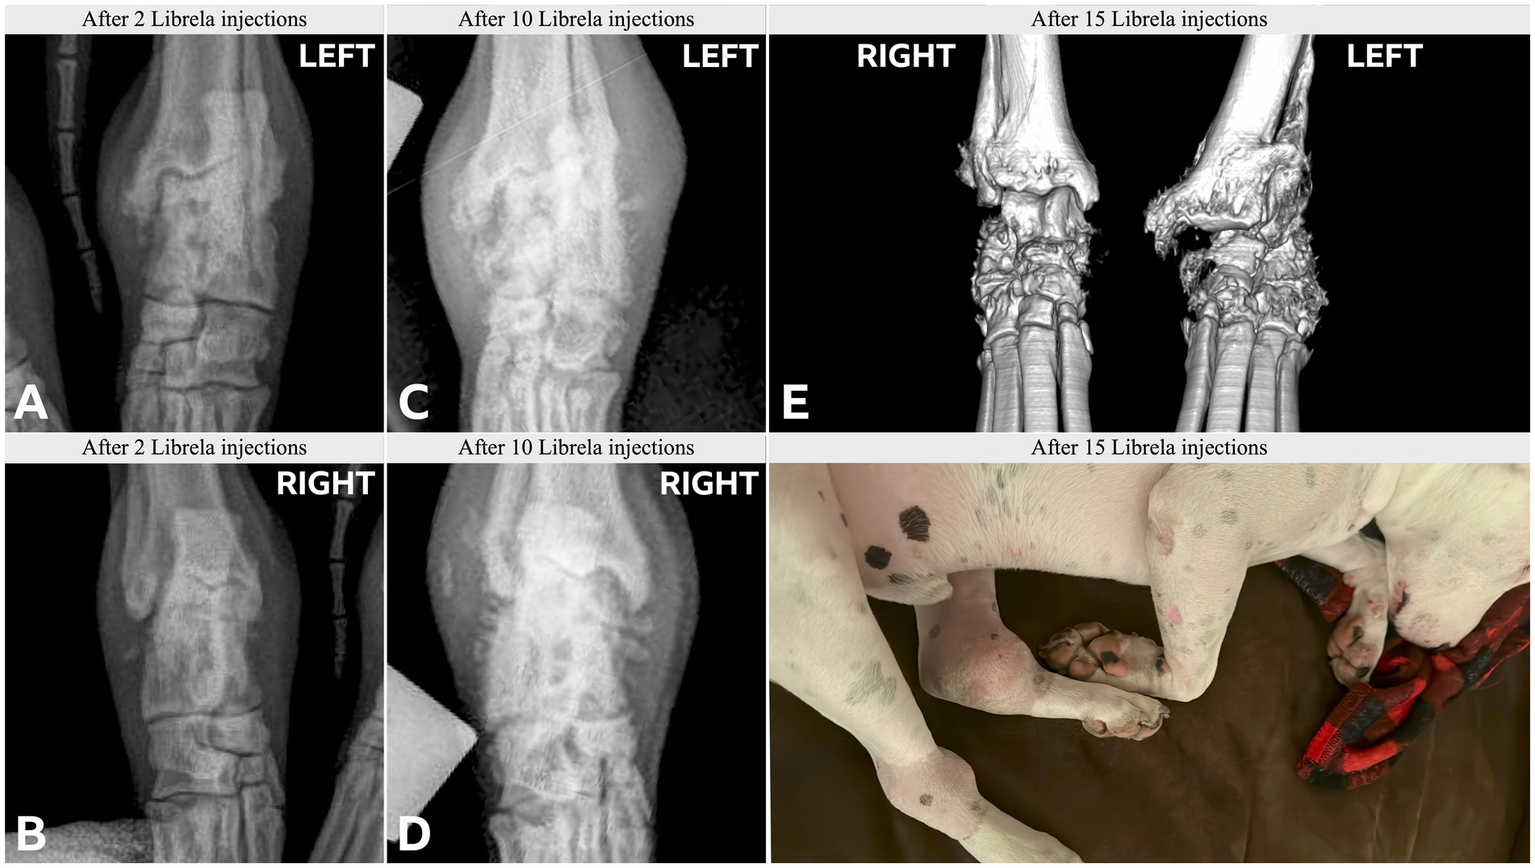

3.3 Case series adjudication outcome

Clinical and radiographic characteristics are summarized in Table 2 and Figures 5–13. Mean ± SD number of Librela doses was 12.7 ± 9.5 (range 1–30), with a dose range of 0.4–0.76 mg/kg (mean 0.62 ± 0.08 mg/kg). Referral for investigation of suspected RPOA was made at least 6 months after Librela initiation in 13/19 cases. Eleven dogs (58%) received regular concurrent NSAIDs. The most frequently affected joint was the elbow (13/19 dogs, 68%), followed by the stifle and hock (two dogs each), and hip (one dog). Seven dogs (37%) sustained pathological fractures, and two (10.5%) had joint luxations. Two dogs with clinically normal hock joints before initiating Librela therapy developed severe non-index hock joint destruction after Librela treatment for elbow OA.

Figure 10

Case 15, an 8-year-old English Bull Terrier treated with Librela for elbow dysplasia developed tarsal swelling and hindlimb lameness within 3 weeks of the first dose. (A,B) Radiographs acquired after 2 Librela injections show moderate bilateral arthrosis which progressed rapidly, culminating in left tibiotarsal luxation (C–E). Synovial fluid analysis ruled out inflammatory arthropathy or tick-borne disease. AER: The MAH filed a report using the diagnostic term “swollen joint”, and misclassified the reaction as not serious and recovered/resolving. Following communication from the attending veterinarian regarding the translation error, the MAH escalated the enquiry to their Global Pharmacovigilance Team, who concluded that the observed pathology was consistent with erosive immune-mediated polyarthritis (IMPA), despite normal synovial fluid test results (Supplementary Figure S8).

Figure 13

Case 19, a 10.5-year-old mixed-breed dog, had 7 Librela injections following right tibial plateau leveling osteotomy (TPLO). Severe joint erosion is evident in the medial femoral condyle (arrow) and tibial plateau, causing screw exposure (chevron). Intractable pain necessitated euthanasia. Surgical site infection and septic arthritis were excluded by necropsy, which revealed findings similar to those reported in human RPOA (20). AER: The attending specialist filed a report for suspected RPOA to the MAH, who submitted an AER using the diagnostic terms “limb non-weight bearing” and “abnormal radiograph finding”.

Histopathological examination of bone and synovial tissue from four dogs revealed no evidence of inflammatory arthropathy, tick-borne diseases, or neoplasia. A pathologist who was invited to compare their findings to those reported in a submitted article on human RPOA (20) commented that the pathological features were similar (21).

Interobserver agreement between diagnostic imaging specialists was substantial (κ = 0.68, 95% CI 0.4–0.97). Both specialists were very suspicious of a potential causal relationship between the observed pathology and Librela treatment in 68% of dogs (13/19). Furthermore, all 18 panelists (including the two diagnostic imagers) were very suspicious of a potential causal relationship between Librela treatment and the observed pathology.